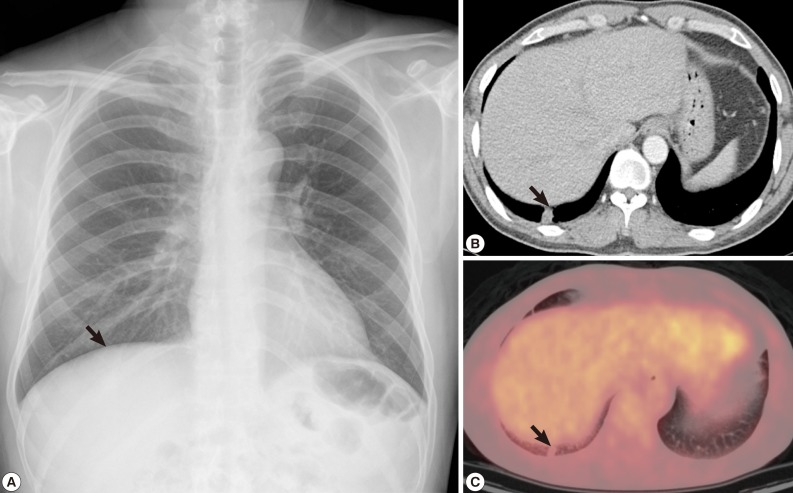

In chest radiography, a nodular opacity was found at the right lower lobe (Fig. 1A). The chest CT showed a 1.2×1.0 cm sized subpleural solitary pulmonary nodule at the right lower lobe. Although it looked as a benign inflammatory nodule such as cryptococcal infection, malignancy could not be excluded (Fig. 1B). On positron emission tomography (PET) image, the small subpleural nodule at the right lower lobe showed minimal increased fludeoxyglucose (FDG) uptake (Standardized uptake value [SUV] 1.25) (Fig. 1C).

Fig. 1

Radiographs of the dirofilariasis patient. (A) A nodular lesion in the right lung found incidentally on chest x-ray. (B) Chest CT demonstrated a solitary pulmonary nodule in the right lower lobe. (C) PET also revealed a small subpleural nodule at the right lower lobe with minimal increased FDG uptake (SUV 1.25).

Fig. 1 Radiographs of the dirofilariasis patient. (A) A nodular lesion in the right lung found incidentally on chest x-ray. (B) Chest CT demonstrated a solitary pulmonary nodule in the right lower lobe. (C) PET also revealed a small subpleural nodule at the right lower lobe with minimal increased FDG uptake (SUV 1.25).